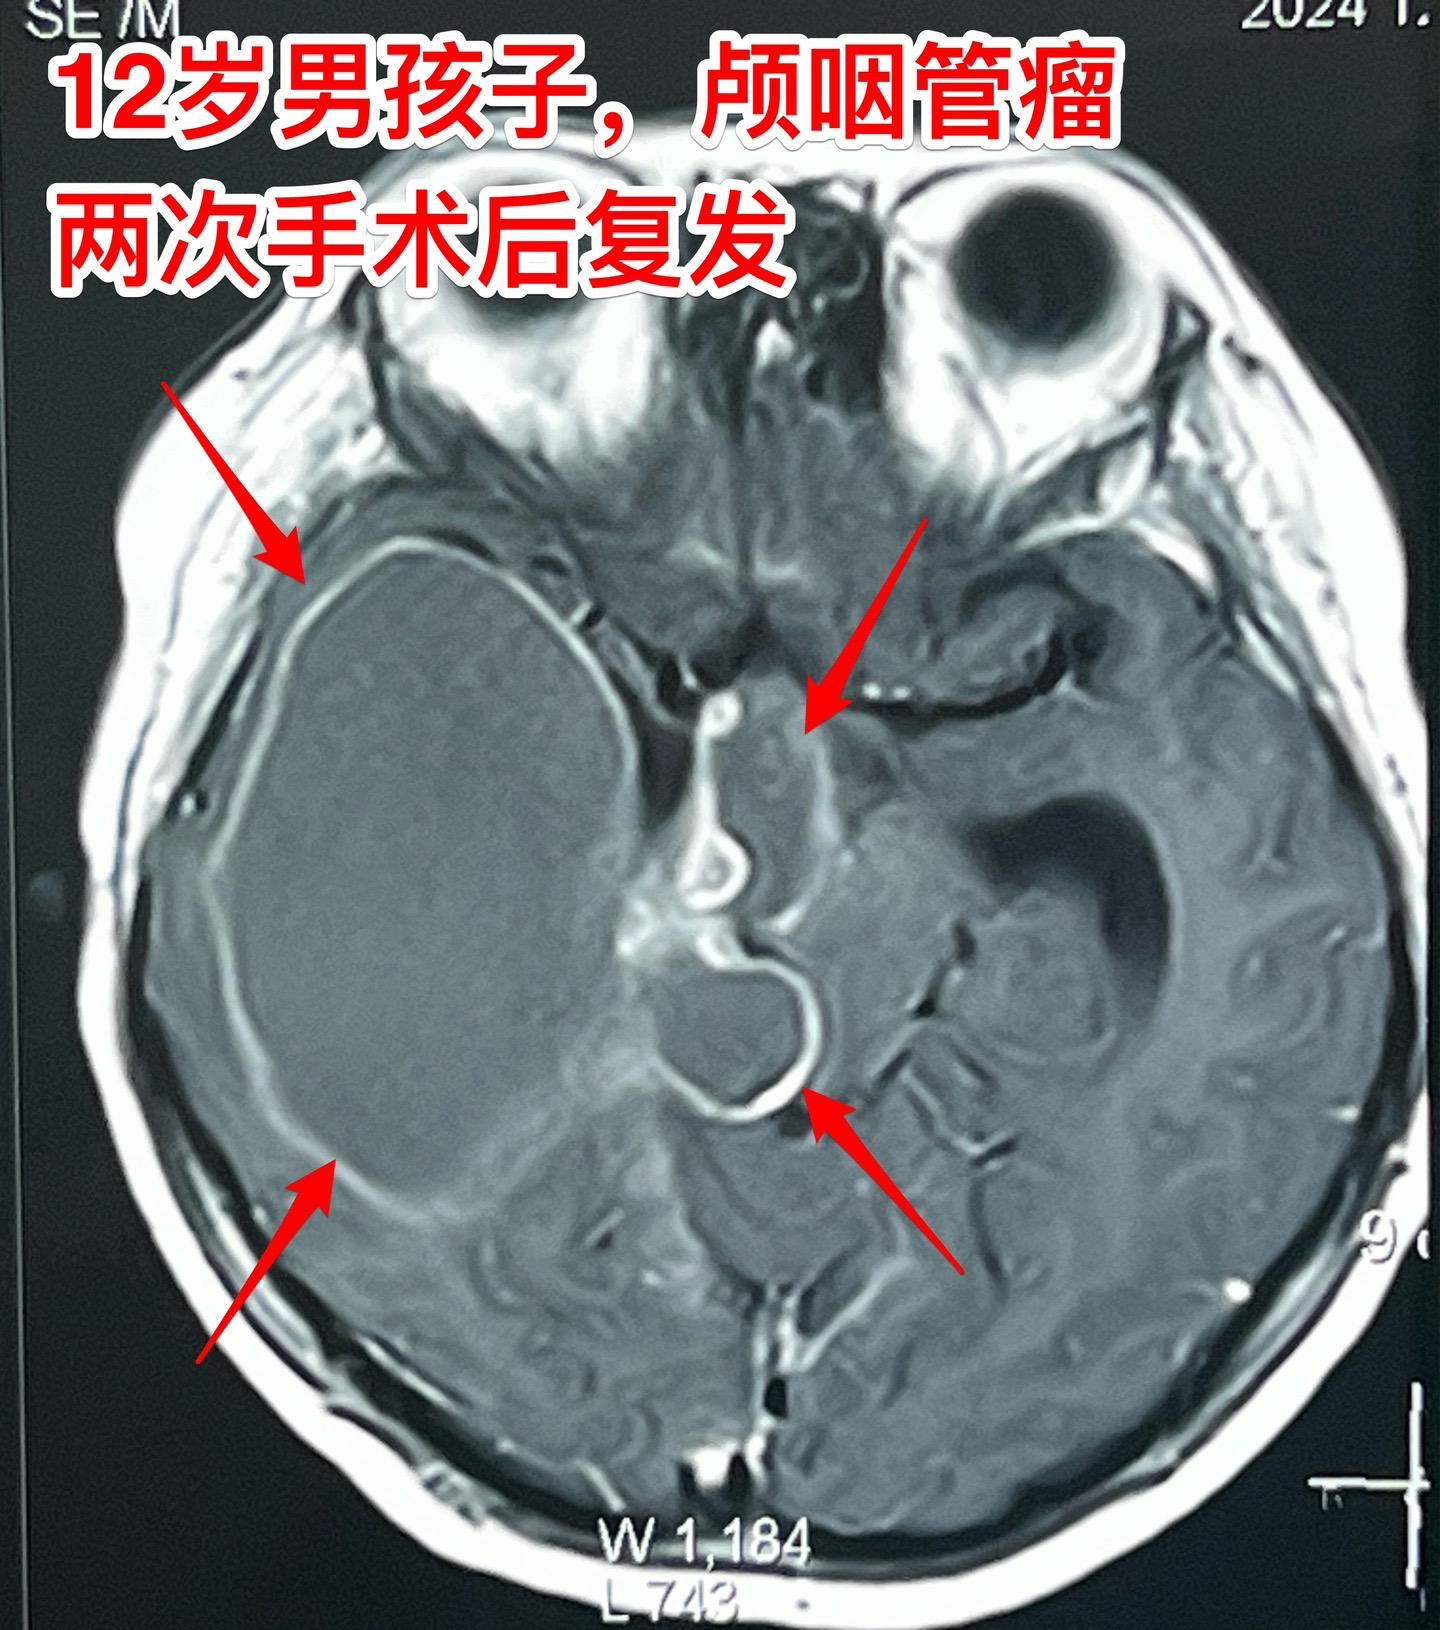

8厘米大的复发颅咽管瘤,也要争取切干净。12岁男孩子,广东省茂名市人。三年时间内先后在广州的两家大医院作了开颅手术,切除颅咽管瘤。2022年8月就发现肿瘤复发了,吃了半年的中药治疗。近一个月间断出现耳鸣、眼前发黑,复查显示颅咽管瘤复发,而且体积巨大,达8厘米。 如图所示,肿瘤压迫脑干和丘脑,切除肿瘤会不会造成病人偏瘫?颅咽管瘤能不能切干净? 2024年12月10日在我科作了开颅手术,手术中看见肿瘤与中脑及丘脑基底节去有粘连,经过仔细分离,将肿瘤完全切除了!手术后病人的四肢活动